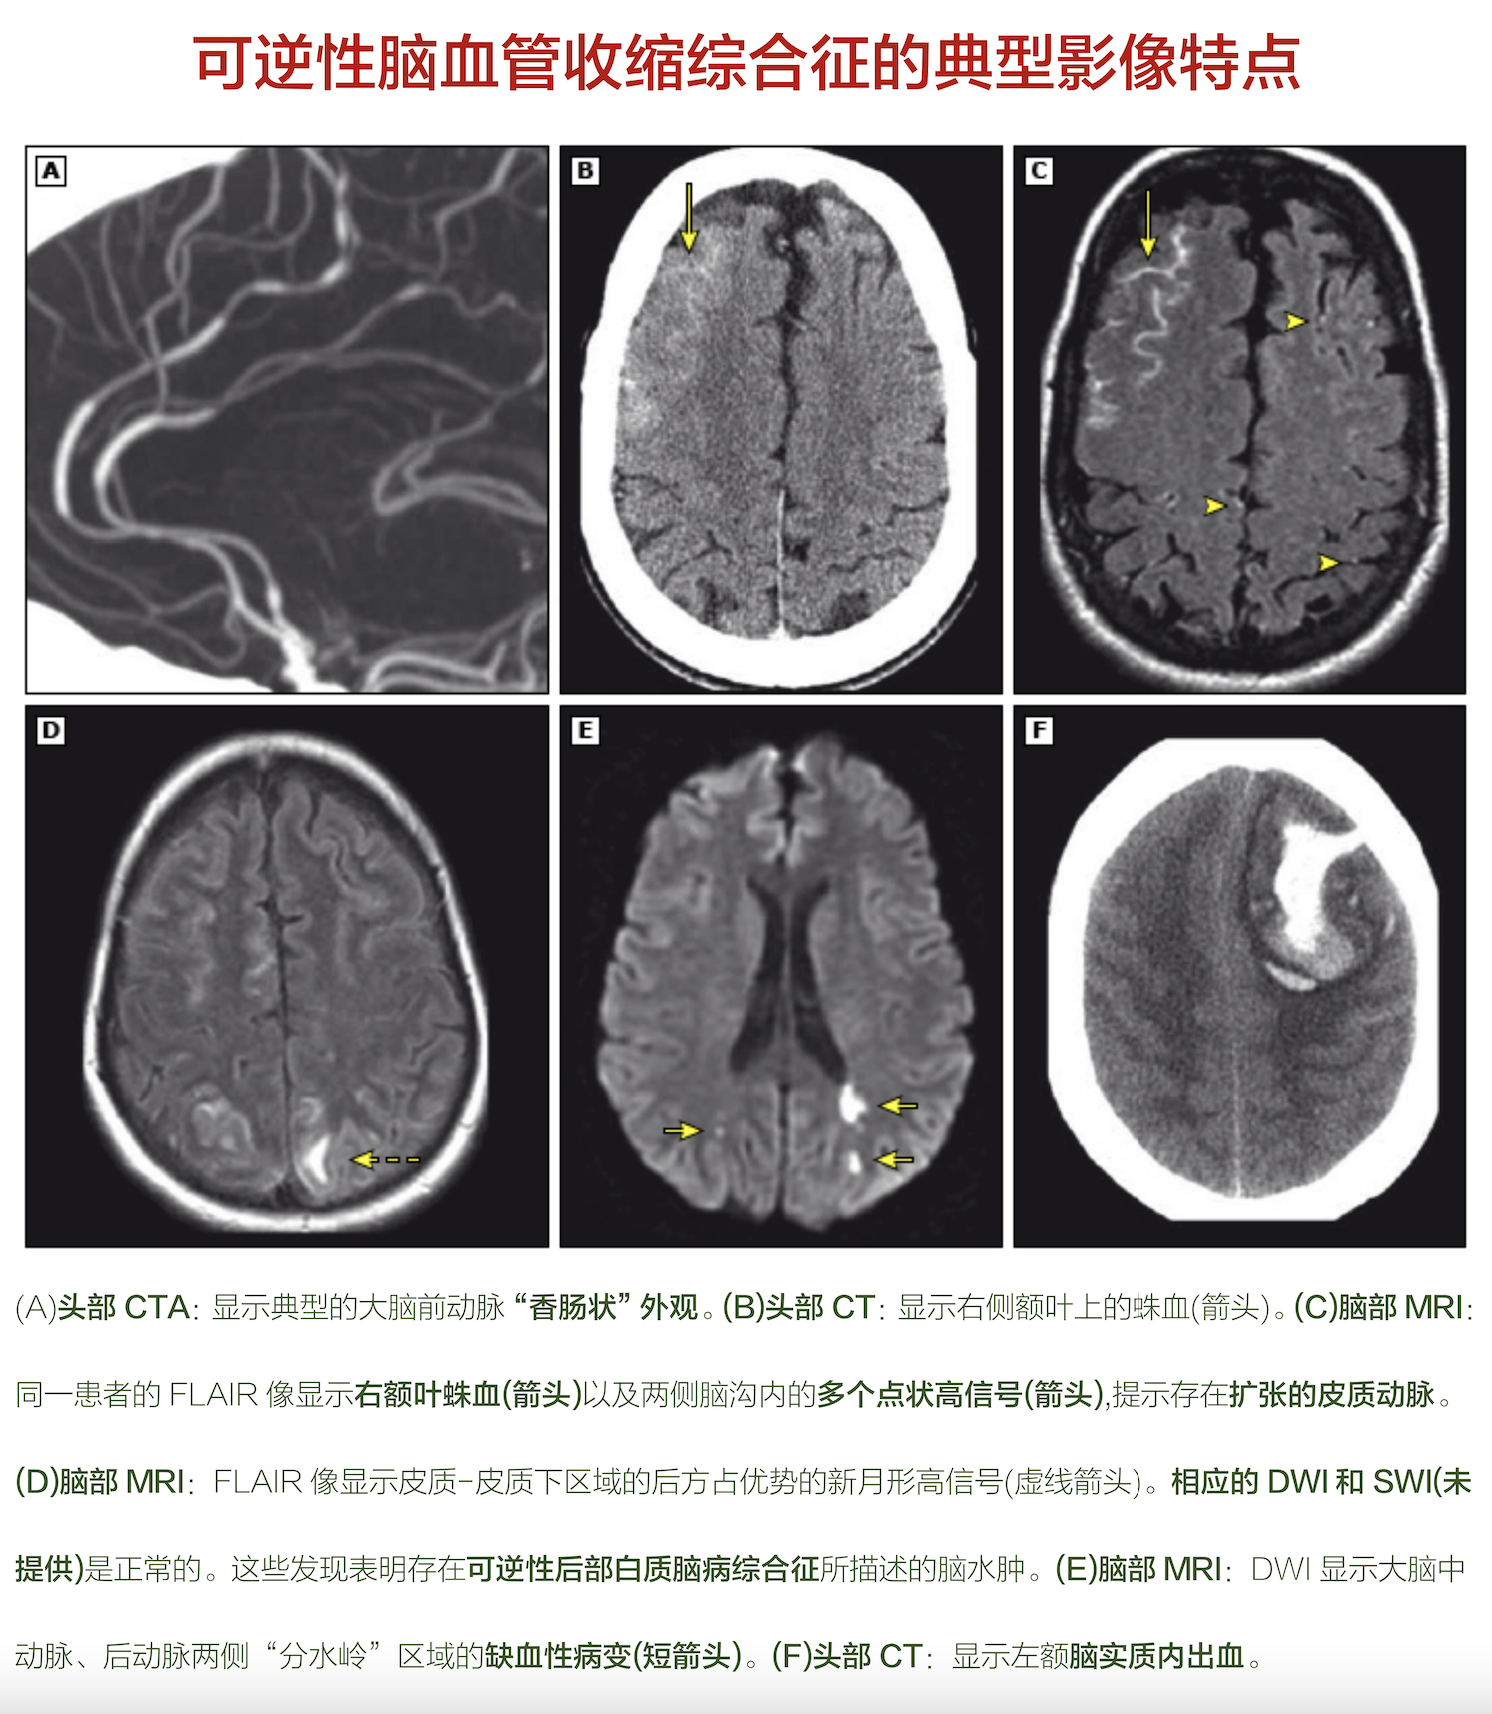

可逆性脑血管收缩综合征典型影像完全.png